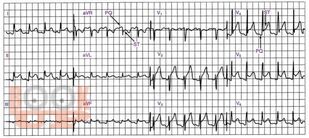

Учебное пособие написано сотрудником кафедры функциональной диагностики ГБОУ ДПО КГМА Минздрава России. В пособии рассмотрены изменения ЭКГ при некоторых заболеваниях и синдромах, таких как острое легочное сердце, перикардит, миокардит, ожирение, дисгормональная кардиомиопатия, острое нарушение мозгового кровообращения и др. Освещены наиболее важные практические аспекты анализа ЭКГ в помощь врачам для проведения дифференциальной диагностики при различной патологии. Пособие предназначено для врачей функциональной диагностики, кардиологов и терапевтов.